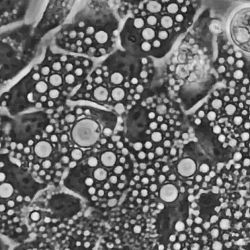

私たちの足元に広がる土壌。そこには、未来の医療を大きく変える可能性を秘めた「宝」が眠っているかもしれません。実は、多くの抗生物質はもともと微生物から発見されました。しかし、薬剤耐性菌の拡大という深刻な問題に直面する一方で、新薬の開発は停滞気味です。その原因の一つは、ほとんどの細菌が実験室では培養できないことでした。この課題を乗り越えるため、研究者たちは土の中に眠る膨大な微生物の「金脈」にアクセスする画期的な方法を開発しました。 彼らのアプローチは、2025年9月12日に『Nature Biotechnology』誌で発表され、これまで謎に包まれていた微生物のゲノム(全遺伝情報)を解き明かし、新たな創薬の可能性を切り開くものとして注目されています。 この研究は、オープンアクセス論文「Bioactive Molecules Unearthed by Terabase-Scale Long-Read Sequencing of a Soil Metagenome(土壌メタゲノムのテラベーススケールのロングリードシーケンシングによって発掘された生理活性分子)」と題されています。 研究チームは、たった一つの森林土壌サンプルから、これまでに全く知られていなかった数百もの細菌の完全なゲノム情報を生成し、さらに2つの新しい抗生物質の候補を発見しました。この成果は、培養不可能な細菌から新薬の候補を大規模に探索する道筋を示し、私たちの環境を形成している広大で未開拓な微生物の世界を明らかにするものです。 「私たちはついに、これまで人類がアクセスできなかった微生物の世界を垣間見る技術を手に入れたのです」と、ロックフェラー大学遺伝子コード化低分子研究所の所長であるショーン・F・ブレイディ博士(Sean F. Brady, PhD)は語ります。「そして、単に情報を見ているだけではありません